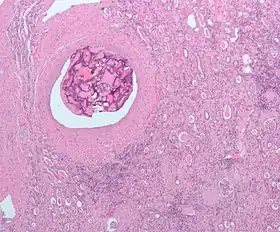

Micrograph of embolic material in the artery of a kidney. The kidney was surgically removed because of cancer. H&E stain.

An embolism is the lodging of an embolus, a blockage-causing piece of material, inside a blood vessel.[1] The embolus may be a blood clot (thrombus), a fat globule (fat embolism), a bubble of air or other gas (gas embolism), amniotic fluid (amniotic fluid embolism), or foreign material.